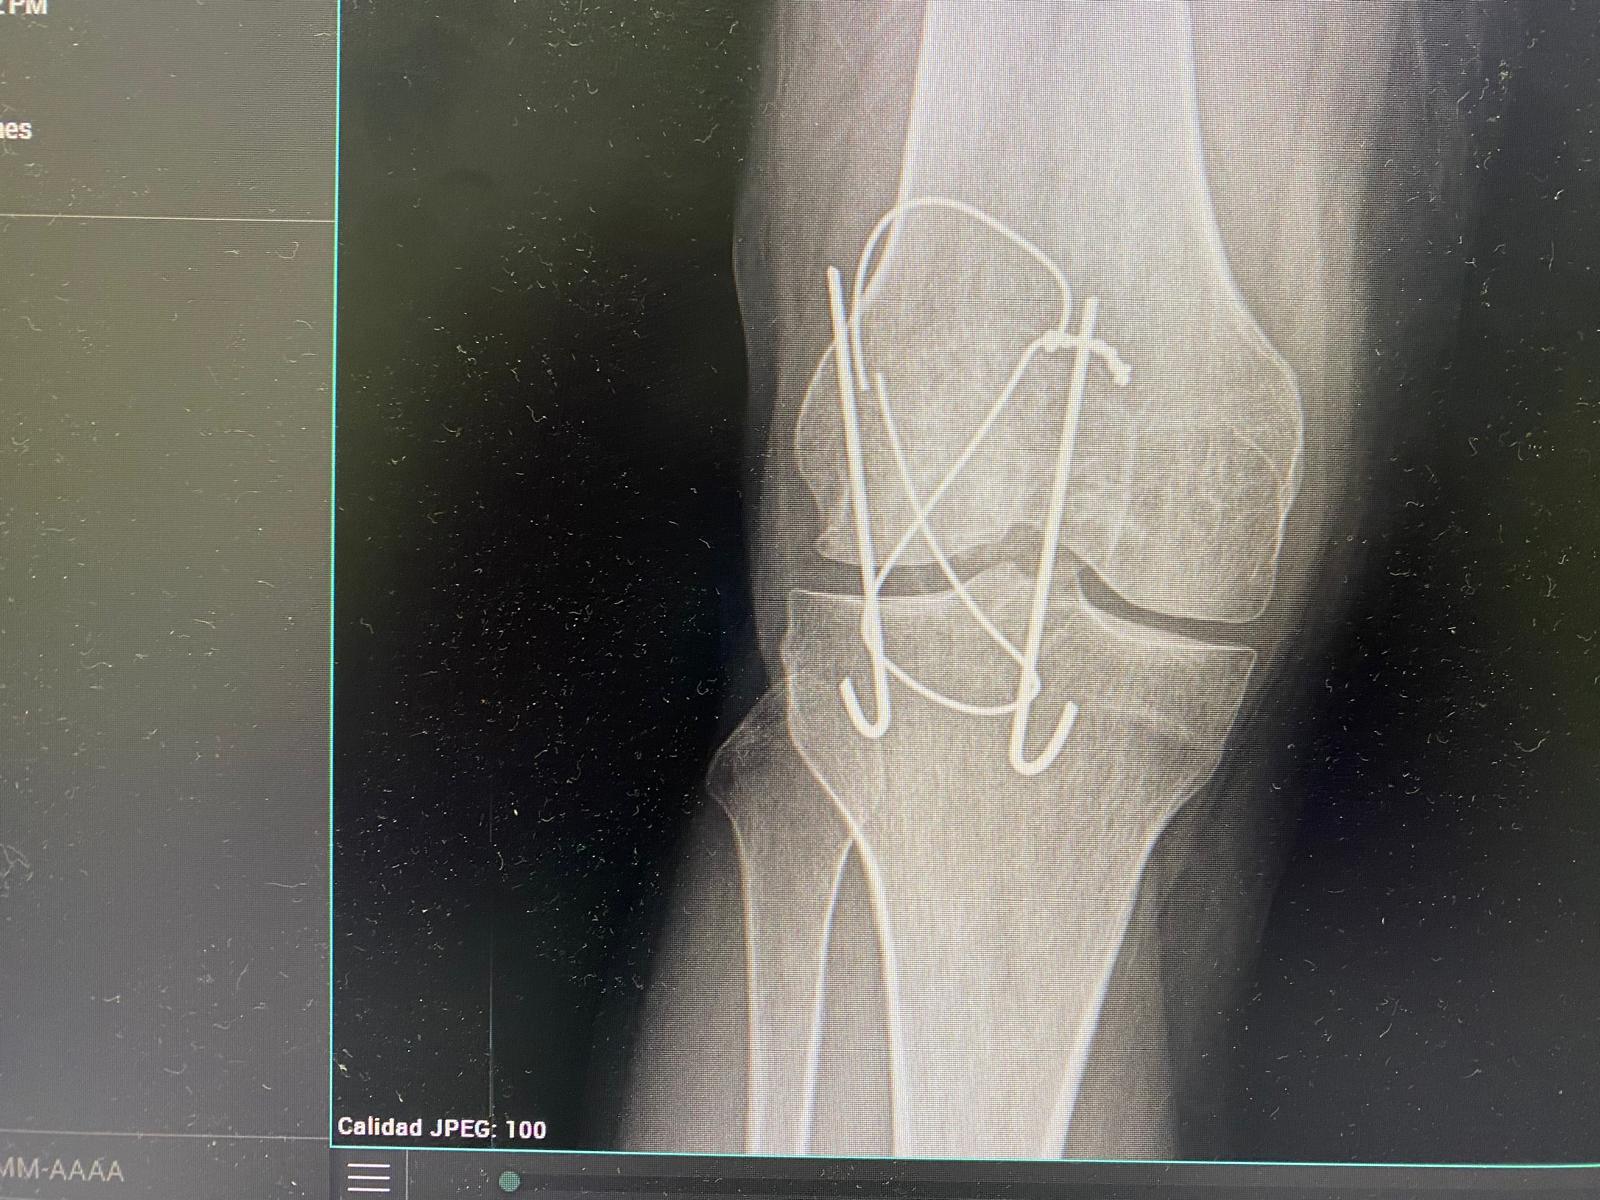

Dolor de rodilla derecha.

Juicio clínico, diagnóstico diferencial, identificación de problemas

Juicio clínico: Hemartros en contexto de rotura de material de osteosíntesis.